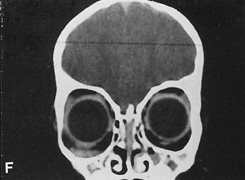

Fig. 14. A,B. Large intraorbital lymphangioma causing proptosis and optic nerve compression in a 2-year-old child. C. View of the left orbit from above after removal of the frontal bone flap, including the supraorbital rim and orbital roof. An extensive exposure of the entire superior and lateral orbit is afforded. The levator and superior rectus complex is being retracted laterally with a muscle hook, whereas the Freer elevator retracts the superior oblique muscle medially. The frontal nerve can be seen running from posterior to anterior over the superior orbit. The orbital mass is exposed in this fashion. D. The fronto-orbital bone flap is wired back in place after completion of the procedure. E. Postoperative appearance of the patient. F. The postoperative CT scan shows complete removal of the lymphangioma. This large and diffuse lesion would have been difficult to remove with any other approach.

A burr hole is placed in the midline just above the orbital rim. This burr hole usually enters the frontal sinus. A second burr hole is placed anteriorly in the temporalis fossa at the junction of the cranium and orbit so that both compartments are exposed. Two or three additional holes are made in the frontal bone connecting the first two holes. The orbital rim is cut from the midline inferiorly, and the lateral orbital rim is cut from the temporalis fossa anteriorly. The dura is freed from the undersurface of the bone flap and is elevated superiorly, and the orbital roof is cracked off. The frontal bone, orbital roof, and supraorbital rim break off in one piece. The brain is retracted superiorly, and the remaining orbital roof is removed with bone rongeurs (see Fig. 14C).

After removal of the bony roof, the periorbita is visible. Typically, the periorbita is thin, and the levator rectus muscle and frontal nerve are visible beneath it. If exposure of the posterior optic nerve is desired, the dura can be elevated over the optic canal. The canal can be unroofed to decompress or explore the optic nerve, and the dura may be opened to view the intracranial optic nerve and the chiasm. At the orbital apex, the annulus may be cut to allow more anterior dissection and removal of the optic nerve in cases such as optic nerve glioma or meningioma. Because the superior orbital fissure and its contents lie lateral to the nerve, the intraconal space is entered on the medial side of the optic nerve. The orbital dissection can be carried out with a minimal amount of brain retraction after the en bloc removal of the frontal bone, supraorbital rim, and orbital roof.

After the dissection, the dura is closed and the frontal bone flap is plated or wired back into position (see Fig. 14D). The orbital roof is functionally restored with the replacement of the bone flap. The sinuses must be sealed off with muscle, pericranium, or other tissue. The coronal flap is closed in layers. The postoperative appearance is unchanged because the bone flap is replaced in one piece. Problems with globe ptosis, enophthalmos, pulsatile proptosis, or meningitis are rare. However, extensive mobilization of the temporalis may result in cosmetically significant temporal atrophy. Orbital apical dissection often results in extraocular motility dysfunction as a result of traction on the third, fourth, or sixth cranial nerves, but cranial nerve function usually recovers unless the nerves have been transected.